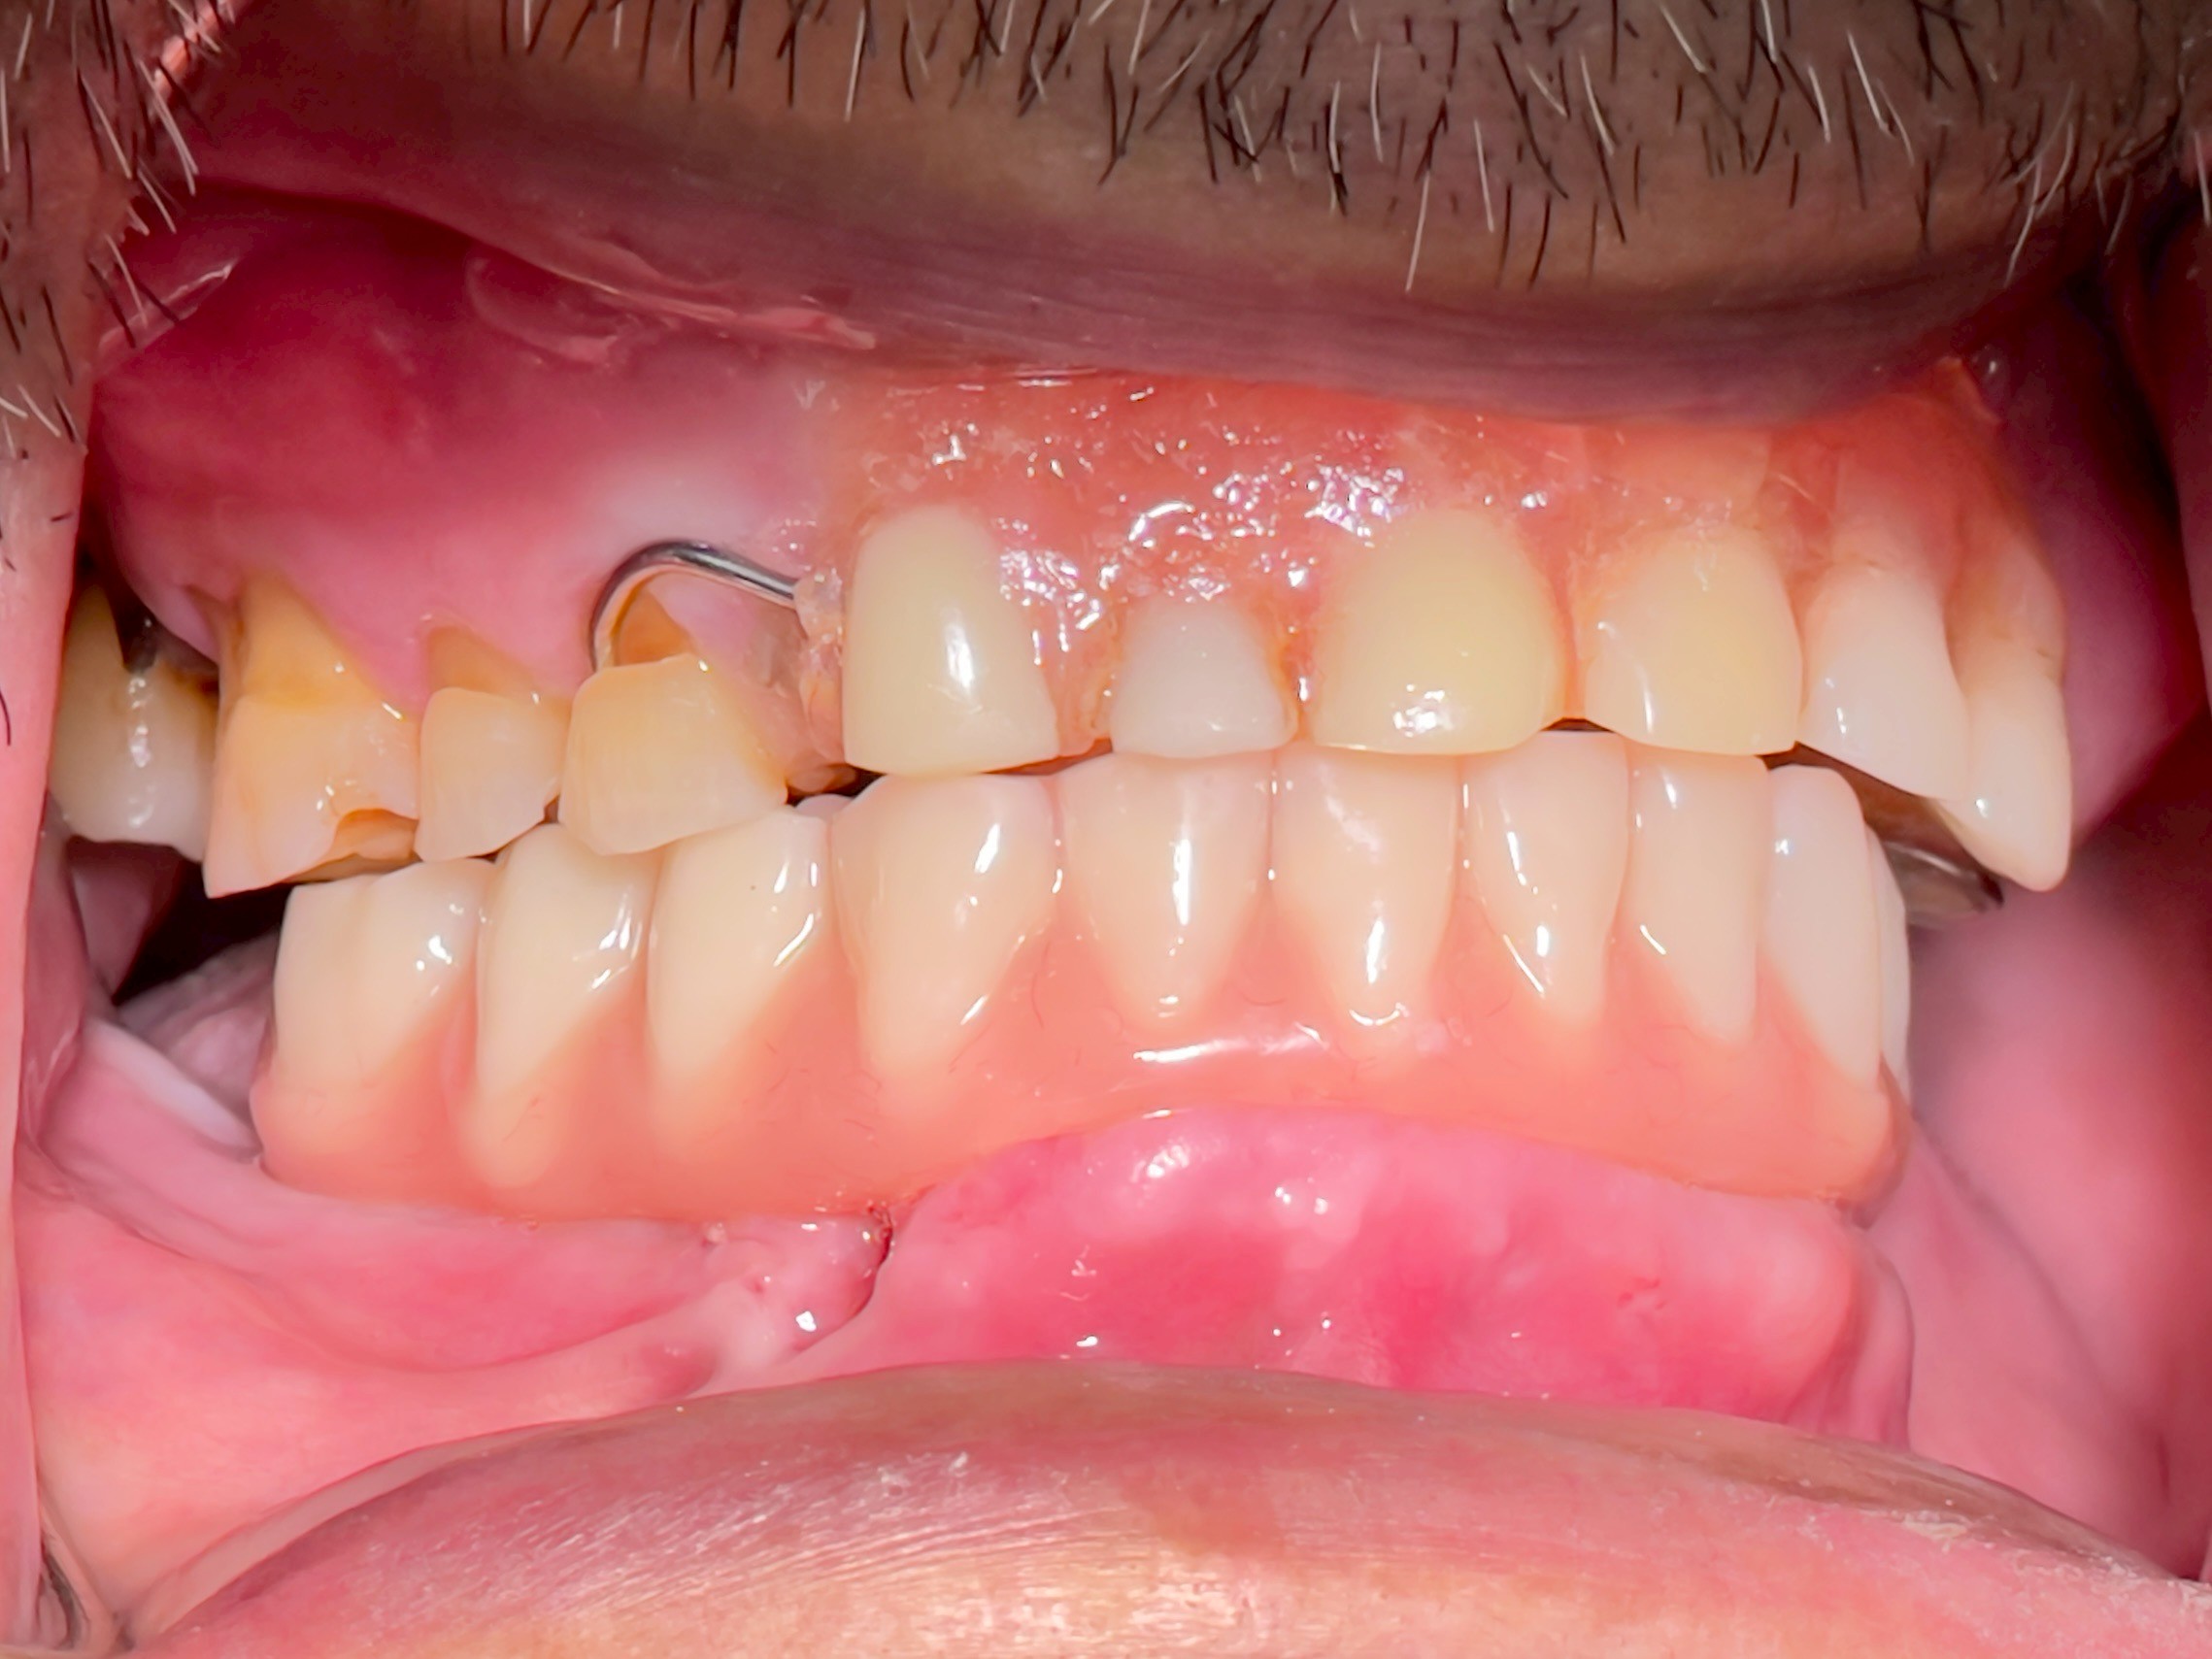

All-on-4 Implants Lower Jaw + Partial Denture Upper Jaw